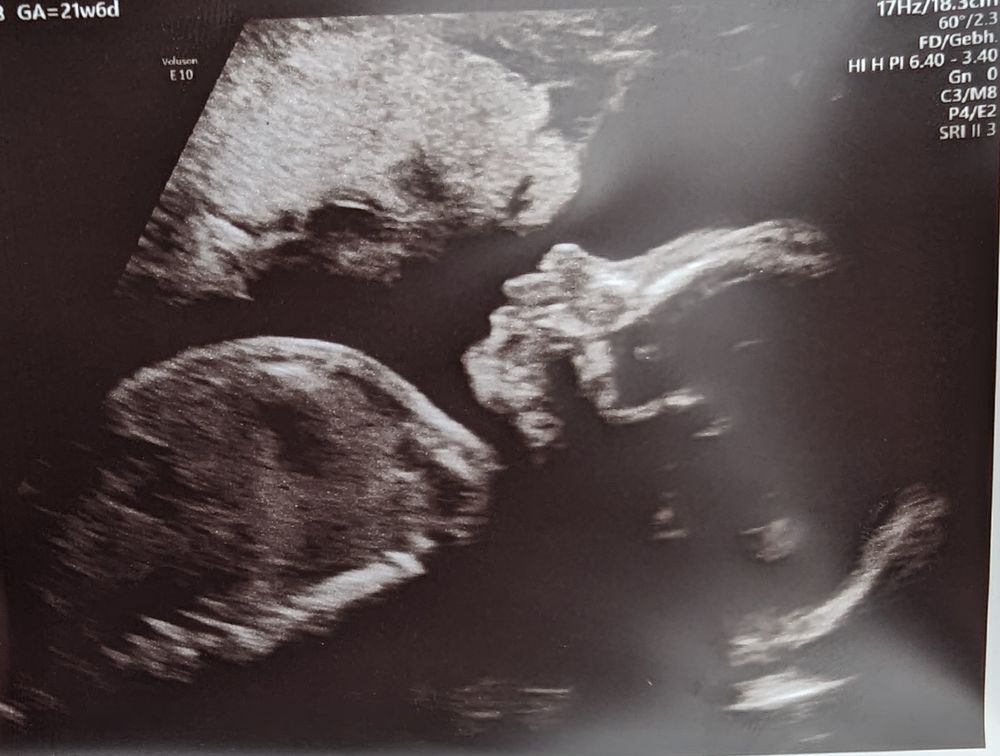

Доп скрининг (21+6) + фото

Вчера съездили на расширенную диагностику. У малыша все хорошо!! Посчитали все косточки, проверили позвоночник, все органы💪 Вес 486г, рост 28 см❤️ Лицо закрывал ручками, но одну фотку "поймали")